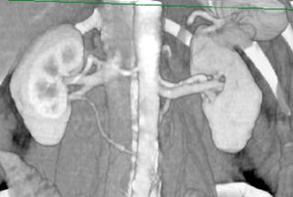

Imagini computertomografice ale vaselor renale: anatomia normala si variante anatomice

Aa.renale normale

Ramificare prehilara a aa.renale stangi

Doua artere renale stangi Doua aa.renale stangi; ramificare prehilara

a aa.renale drepte; v.renala stg. retroaortica

Doua aa.renale stangi

A.renala accesorie stanga Aa.renale multiple

Rinichi pentru transplant cu multiple aa. renale

bilateral

Vene renale normale

A doua v. renala stanga se varsa in iliaca V.renala stanga bifida

comuna stanga

V.renala stanga retroaortica V.renala stanga retroaortica si v.genitala

foarte voluminoasa